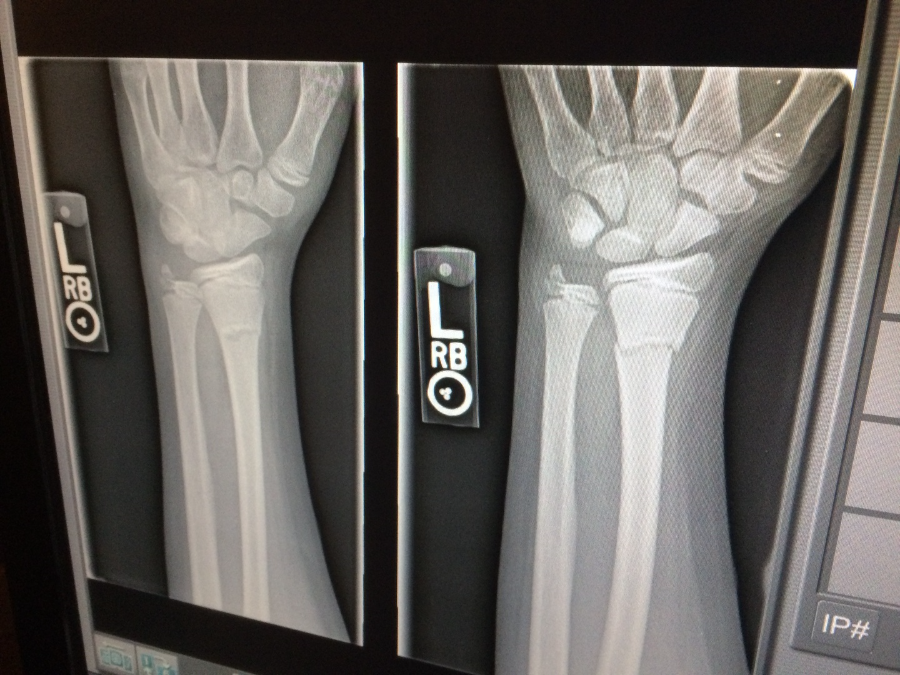

Zur Untersuchung steht uns ein modernes System zur digitalen Röntgendiagnostik zur Verfügung, welches schnell und strahlungsarm arbeitet, und die Aufnahmen in guter Qualität - bei Bedarf auf CD gebrannt werden können - um Sie Ihnen bei einer erforderlichen Krankenhausbehandlung mitgeben zu können.